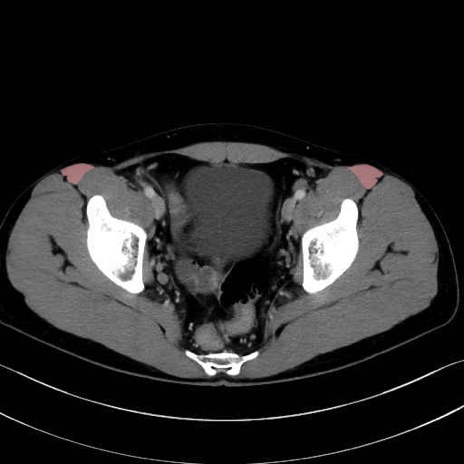

大腿筋膜張筋 (Tensor fasciae latae)

縫工筋 (Sartorius)